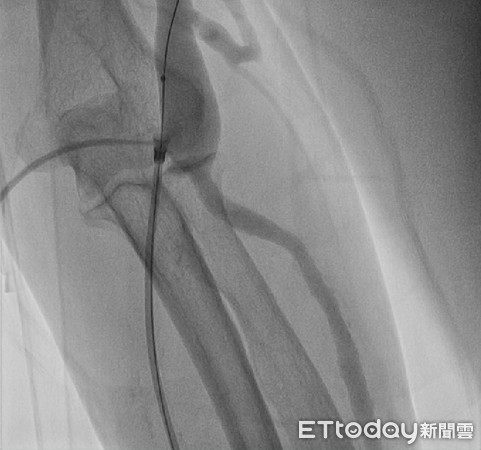

▲亞大醫院心臟血管外科主任劉殷佐為患者通血管。(圖/亞大醫院提供)

劉殷佐指出,通常自體廔管若保養得當,通常可使用10年以上,但若沒有適當照護廔管,有時會發生血管狹窄的情形,嚴重者恐因狹窄引起血栓,出現生命危險,以林姓患者為例,因患者的廔管有出現滲血、阻塞等情形,必須在短時間內透過氣球擴張術等方式將血管撐開,以便血液流通,治療時間約15分鐘,結束後即可返家。